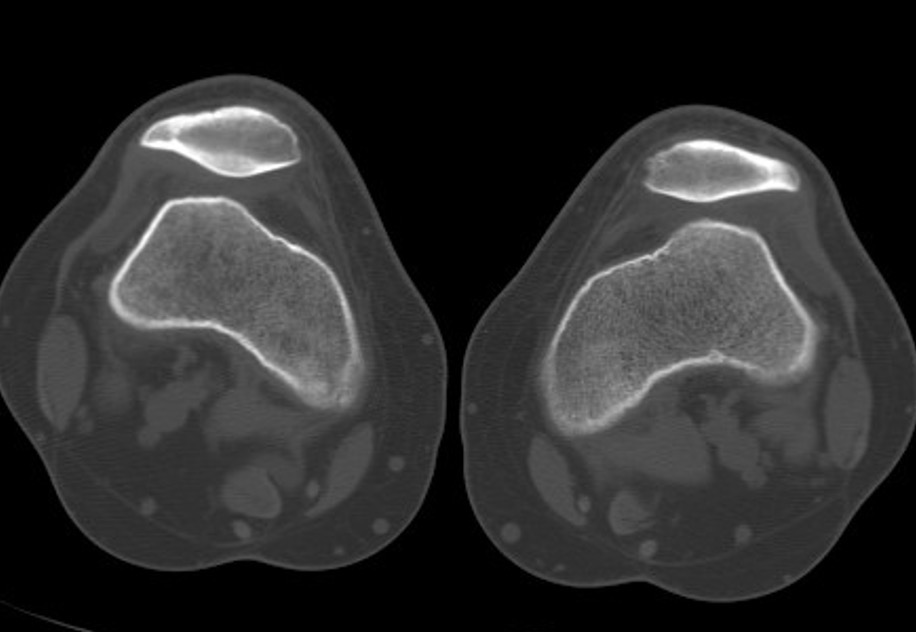

CT

Lateral subluxation / trochlea dysplasia

Tibial Tuberosity Trochlea Groove (TTTG)

- superimpose 2 axial slices

- axial slice of trochlea

- line perpendicular through trochlea groove

- perpendicular line through tibial tubersity